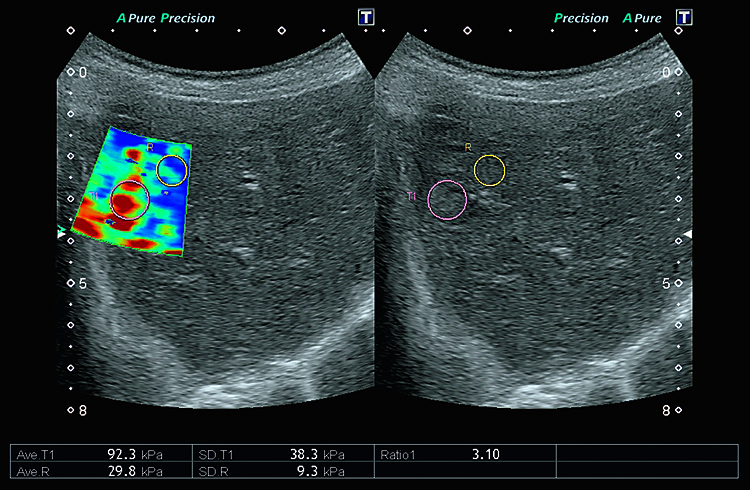

Технология сдвиговых волн Canon Medical Systems обеспечивает количественное измерение и динамическое визуальное отображение жесткости ткани в различных клинических условиях, начиная от брюшной полости и заканчивая исследованиями мелких деталей. Высокоточный и воспроизводимый инструмент обеспечивает полностью интегрированные измерения и отчеты для полной интеграции в ваш клинический рабочий процесс.

Технология эластографии с функцией сохранения исходных данных в формате RAW предназначена для локализации и оценки жесткости пальпируемых образований с непревзойденной точностью.

Эластография в реальном времени. Наше комплексное решение для эластографии с функциональностью необработанных данных помогает локализовать и оценивать ощутимые массы с высокой точностью, чувствительностью и воспроизводимостью в широком диапазоне клинических условий. Различные параметры эластичности ткани могут быть определены количественно или иметь цветовую кодировку на параметрических изображениях, делая подозрительные изменения ткани количественными и видимыми на ультразвуковом изображении.

Индикатор качества помогает вам правильно подать давление на датчик, гарантируя, что вы всегда получаете надежные результаты.